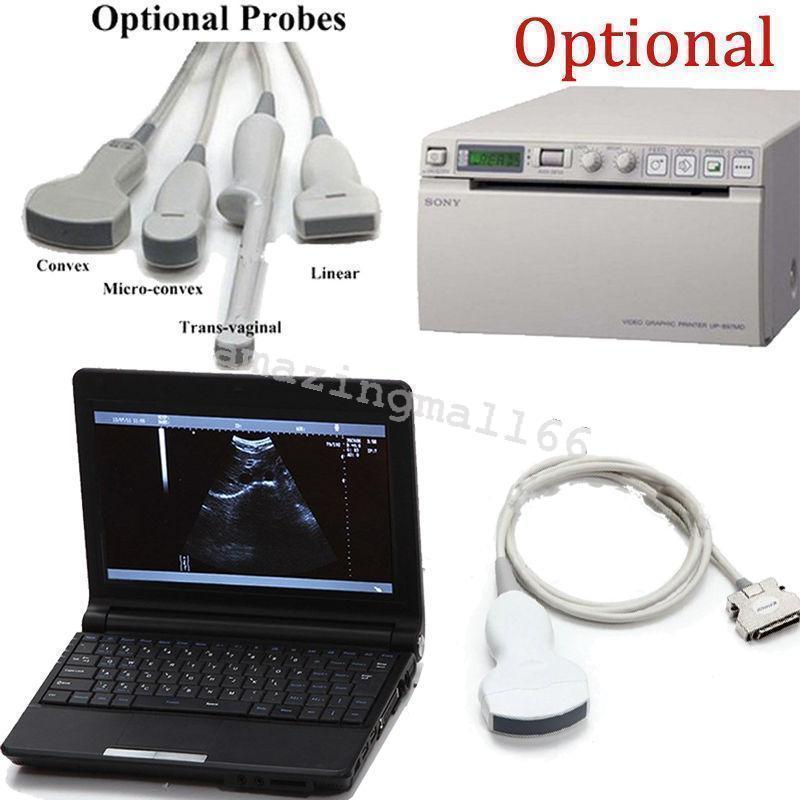

Save $ 480.42

DIAGNOSTIC ULTRASOUND MACHINES FOR SALE

Veterinary VET Laptop Ultrasound Scanner Machine Rectal Linear Probe +3D Animals 190891052124

Sale price$ 2,188.57

Regular price$ 2,668.99